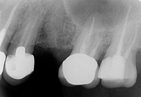

植牙後務必要注意口腔保健,尤其一發現疑似牙周病的徵兆,如刷牙出血、牙齦浮腫、口臭等現象,最

好馬上就醫治療,以免影響植體功能。